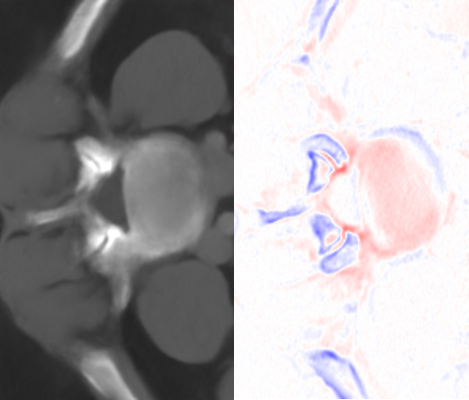

Figure 6: Visual comparisons of different methods against AMI. The difference maps are provided to the right of the results for better visualization. Images are best viewed when magnified.

Table 4 summarizes the performance of different implementations against AMI, evaluated on Isag(x,y,z)subscript𝐼𝑠𝑎𝑔𝑥𝑦𝑧I_{sag}(x,y,z), which we find to have better quantitative results than Icor(x,y,z)subscript𝐼𝑐𝑜𝑟𝑥𝑦𝑧I_{cor}(x,y,z) for all methods. For both rz=4subscript𝑟𝑧4r_{z}=4 and rz=6subscript𝑟𝑧6r_{z}=6, we found improvement in image quality from AMI over other methods, while Meta-SR and RDN have comparable performance. Despite the higher parameter number, MDSR ranked last due to using different substructures for different upsampling factors. For visual demonstration, we can see in Fig. 6 that AMI is able to recover the separation between the bones of the spine, while other methods lead to erroneous recovery where the bones are merged together. Compared to Meta-SR, AMI generates HW𝐻𝑊HW times less filter weights in its filter generation stage. With finite memory, this allows for GPUs to handle more slices in parallel, and achieve faster inference time per volume.